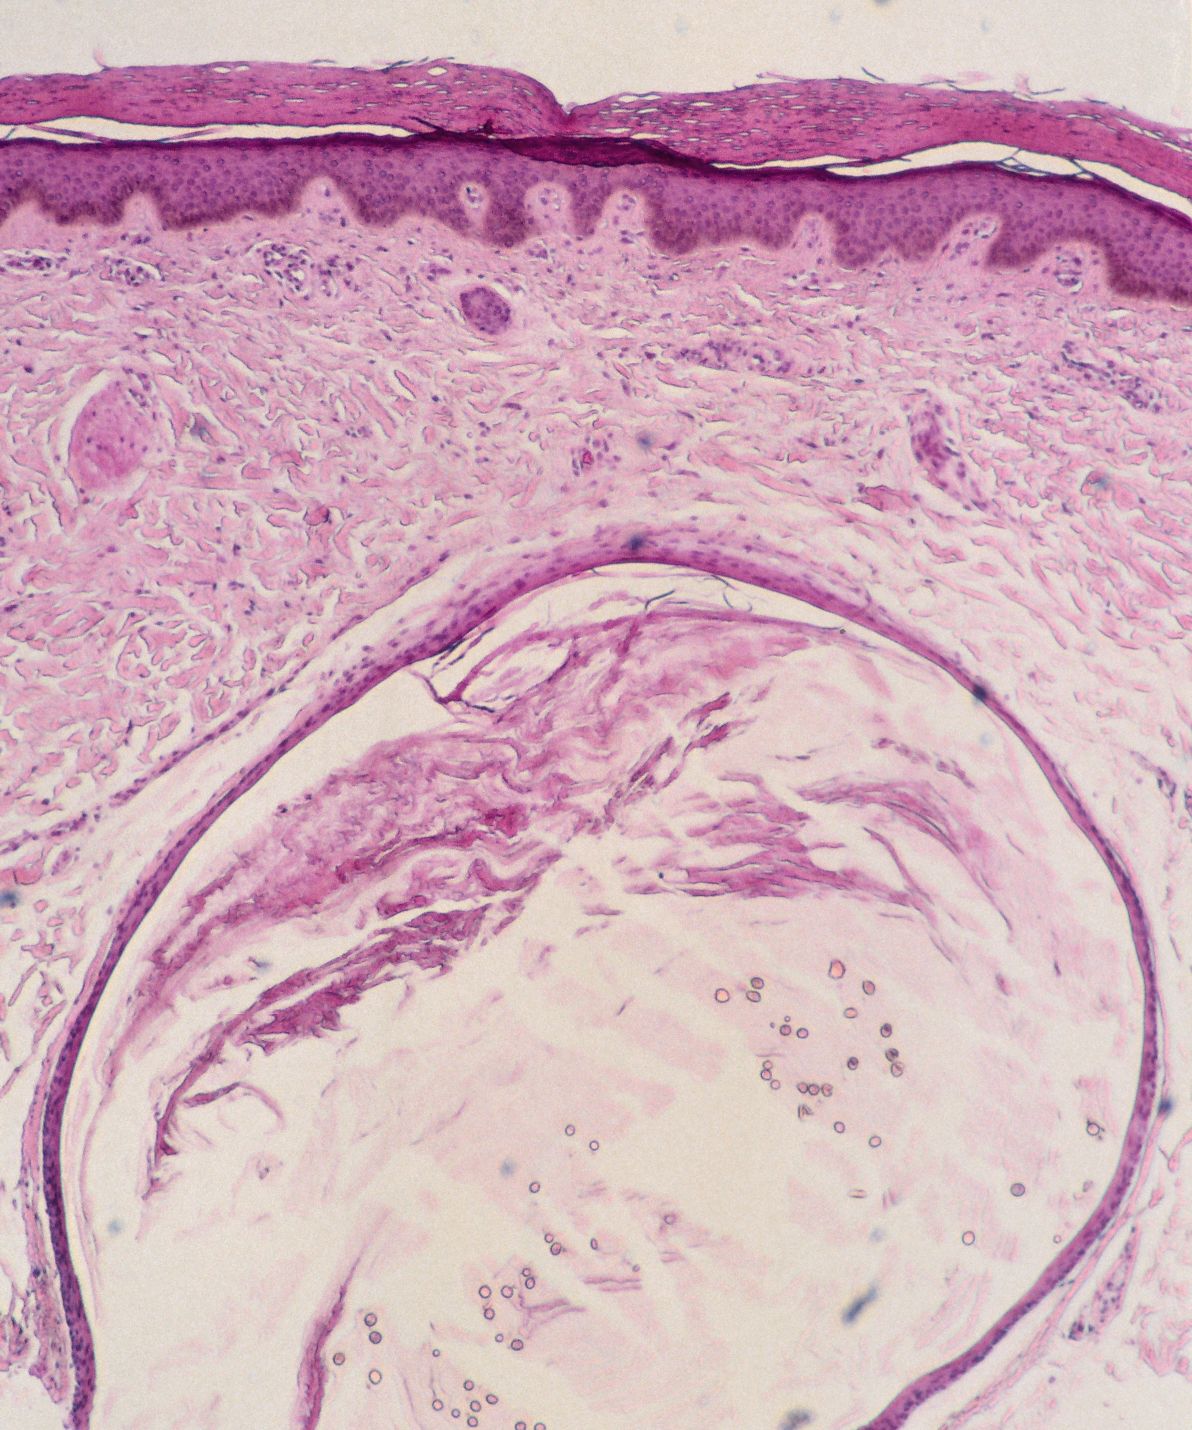

vellushaar cyste (PA) |

PA: kleine trichilemmale / epidermale cysten, uitgaande

van een haarfollikel, gevuld met hoorn en talrijke kleine vellusharen.